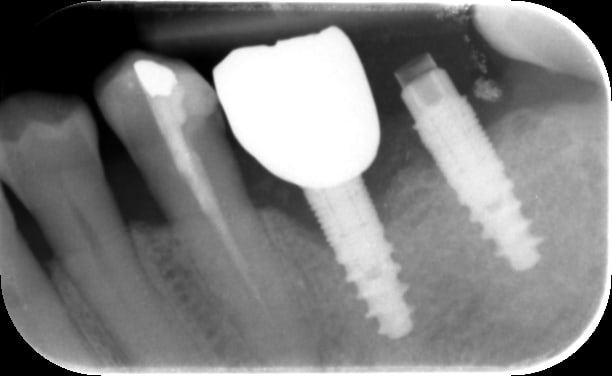

J'essaie d'identifier le type de ces deux implants, après recherche sur what... il me semble reconnaître de l'Euroteknika mais je n'en suis pas sûr du tout, un peu d'aide me serait précieuse.

Ta radiographie est pas super nette...mais il me semble deviner les spires qui se dédoublent en haut.....et si c’est bien ça alors c’est un tiologic dentaurum

https://www.dentaurum.de/fra/concept-du-systeme-tiologic-32770.aspx